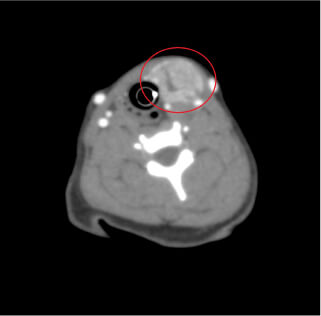

- 頭部

- 水頭症、耳道疾患、

歯科疾患、鼻腔内疾患、

意識障害